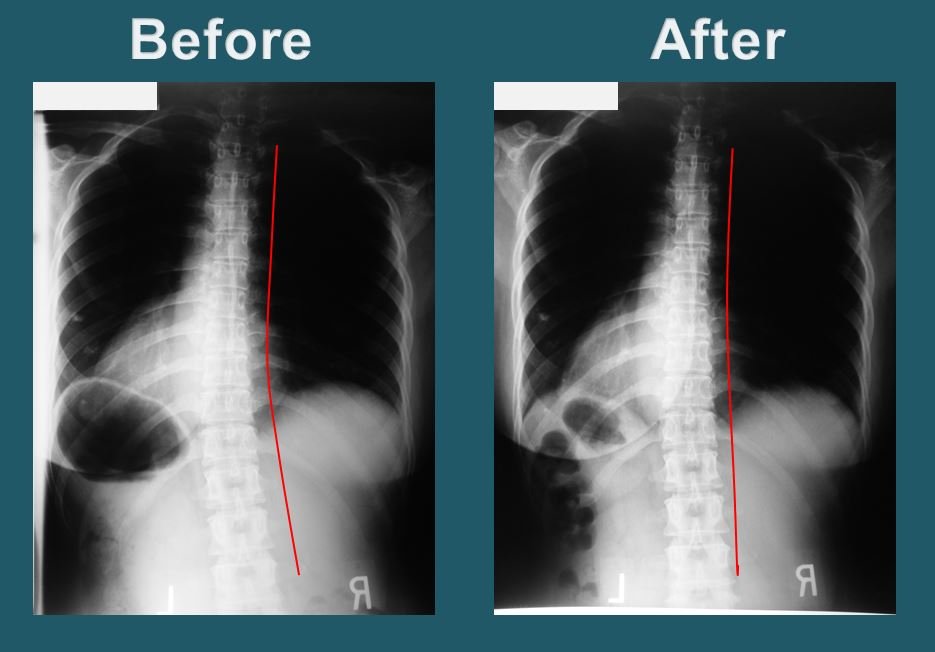

Side-scroll through X-rays captured before and after treatment.